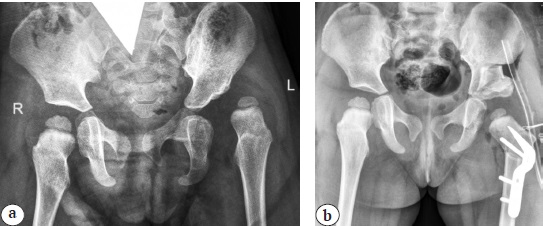

Patients of both groups underwent a clinical examination, typical for this orthopedic disease of the hip joint, and an X-ray examination, which consisted of performing radiography of the hip joints in the frontal view, Lauenstein position, and abduction and internal rotation of the lower extremities before and after surgical treatment. In this study, we focused on the assessment of the X-ray anatomical structure of the acetabulum after surgical correction. X-ray measurements were used to assess the acetabular index (AI), Wiberg angle, caput-collum-diaphyseal angle (CCDA), anteversion angle of the proximal femur (AA), bone coverage degree, acetabular depth (AD), and pelvic height (PH) (Fig. 1).

Fig. 1. Calculation of indicators in a patient with hip dysplasia IHDI type IV: a — acetabular depth: yellow line — the inner contour of the acetabulum; black — the line connecting the lateral edge of the acetabulum with the lower edge of the “tear drop figure”; blue (the depth of the acetabulum) — perpendicular from the medial part of the acetabulum to the black line; b — the pelvic height